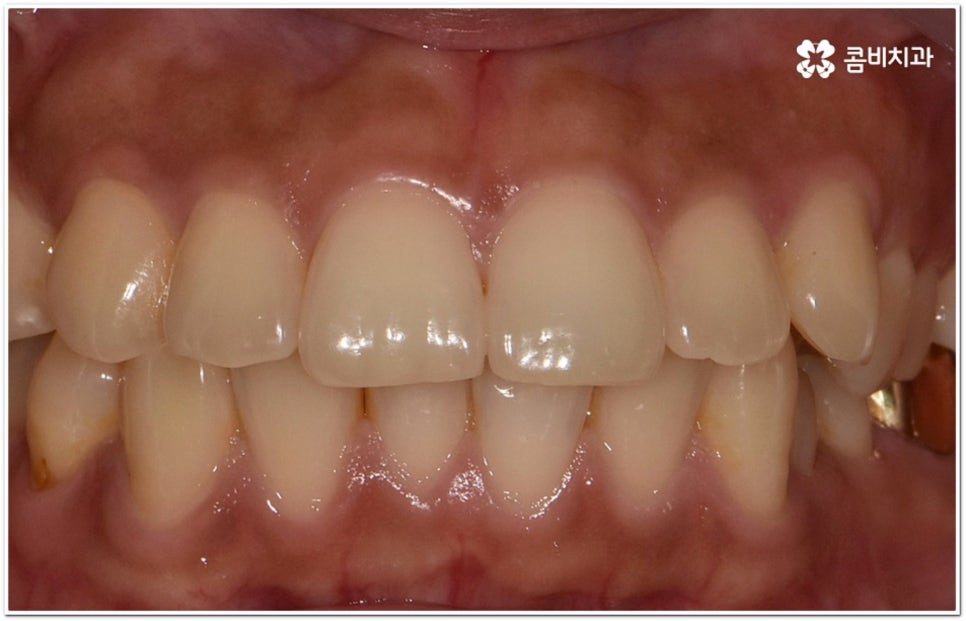

옆에서 봤을 때 코나 턱보다 입이 더 튀어나와 있으면 뾰루퉁한 인상을 줄 수 있고 웃을 때 잇몸이 드러나 콤플렉스처럼 느껴질 수 있는데요. 정도가 심한 경우 입을 꼭 닫고 있기 어려워 자기도 모르게 구호흡을 하게 되면서 여러 구강 질환 및 구취를 유발하게 될 수도 있기 때문에 이러한 심미적 또는 기능적인 이유로 돌출입교정치과 를 알아보시는 분들이 많이 있을 거예요.

이때 위아래 치아가 맞물리는 데는 별다른 문제가 없고 앞니 등 치아가 조금 뻐드러진 상황이라면 각도만 개선해도 되지만 잇몸뼈 자체가 나와 있고 교합에도 문제가 있다면 종합적인 해결이 필요할 수 있는데요.

단순히 치아가 튀어나온 각도를 고친다고 돌출입 개선이 되지는 않고 구조적 골격적인 원인을 파악하여 해결해야 추후 턱관절 건강 부분에까지 좋지 않은 영향을 미치는 것을 막을 수 있습니다.